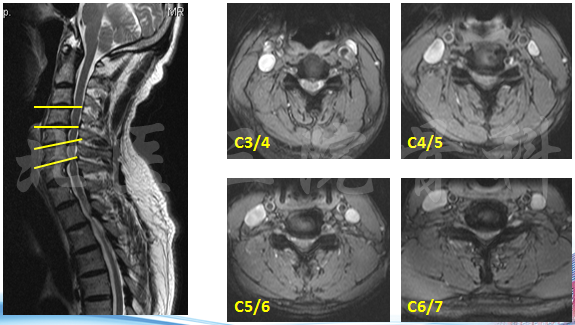

影像学检查

MRI

诊断:脊髓型颈椎病;颈椎间盘突出 (C3-C6);发育性颈椎管狭窄。

治疗:Anterior—C3-6ACDF;Posterior—Laminoplasty、Lami +fusion。